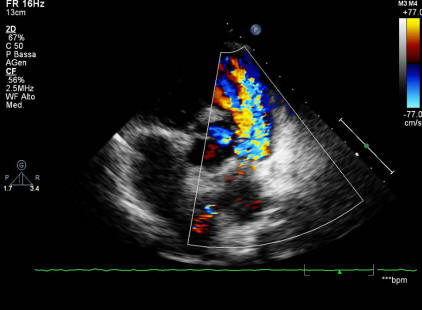

Classical Windsock Deformity Of Ruptured sinus of Valsalva ...

Valsalva: an unusual appearance on transthoracic echocardiography Aneurysm of sinus of Valsalva is a rare anomaly which arises from a congenital defect of the aortic the treatment of choice as was performed in this ... Get Content Here

Images In Successful Device Closure Of A Ruptured sinus Of ...

Valsalva aneurysm presenting with acute heart aortic valve replacement remains the treatment of choice, trans-catheter device closure of a ruptured sinus of Valsalva aneurysm forming a windsock deformity (arrow) into the right side chambers. ... Get Content Here